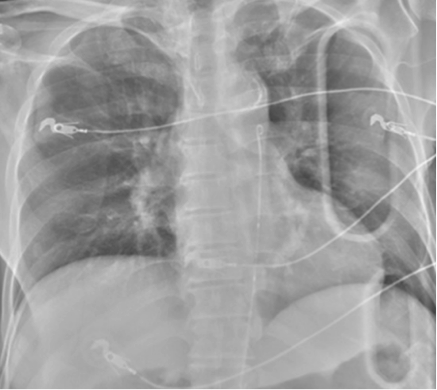

o   CXR to visualize balloon above the diaphragm (at level of ~xiphoid)

reboa2.png